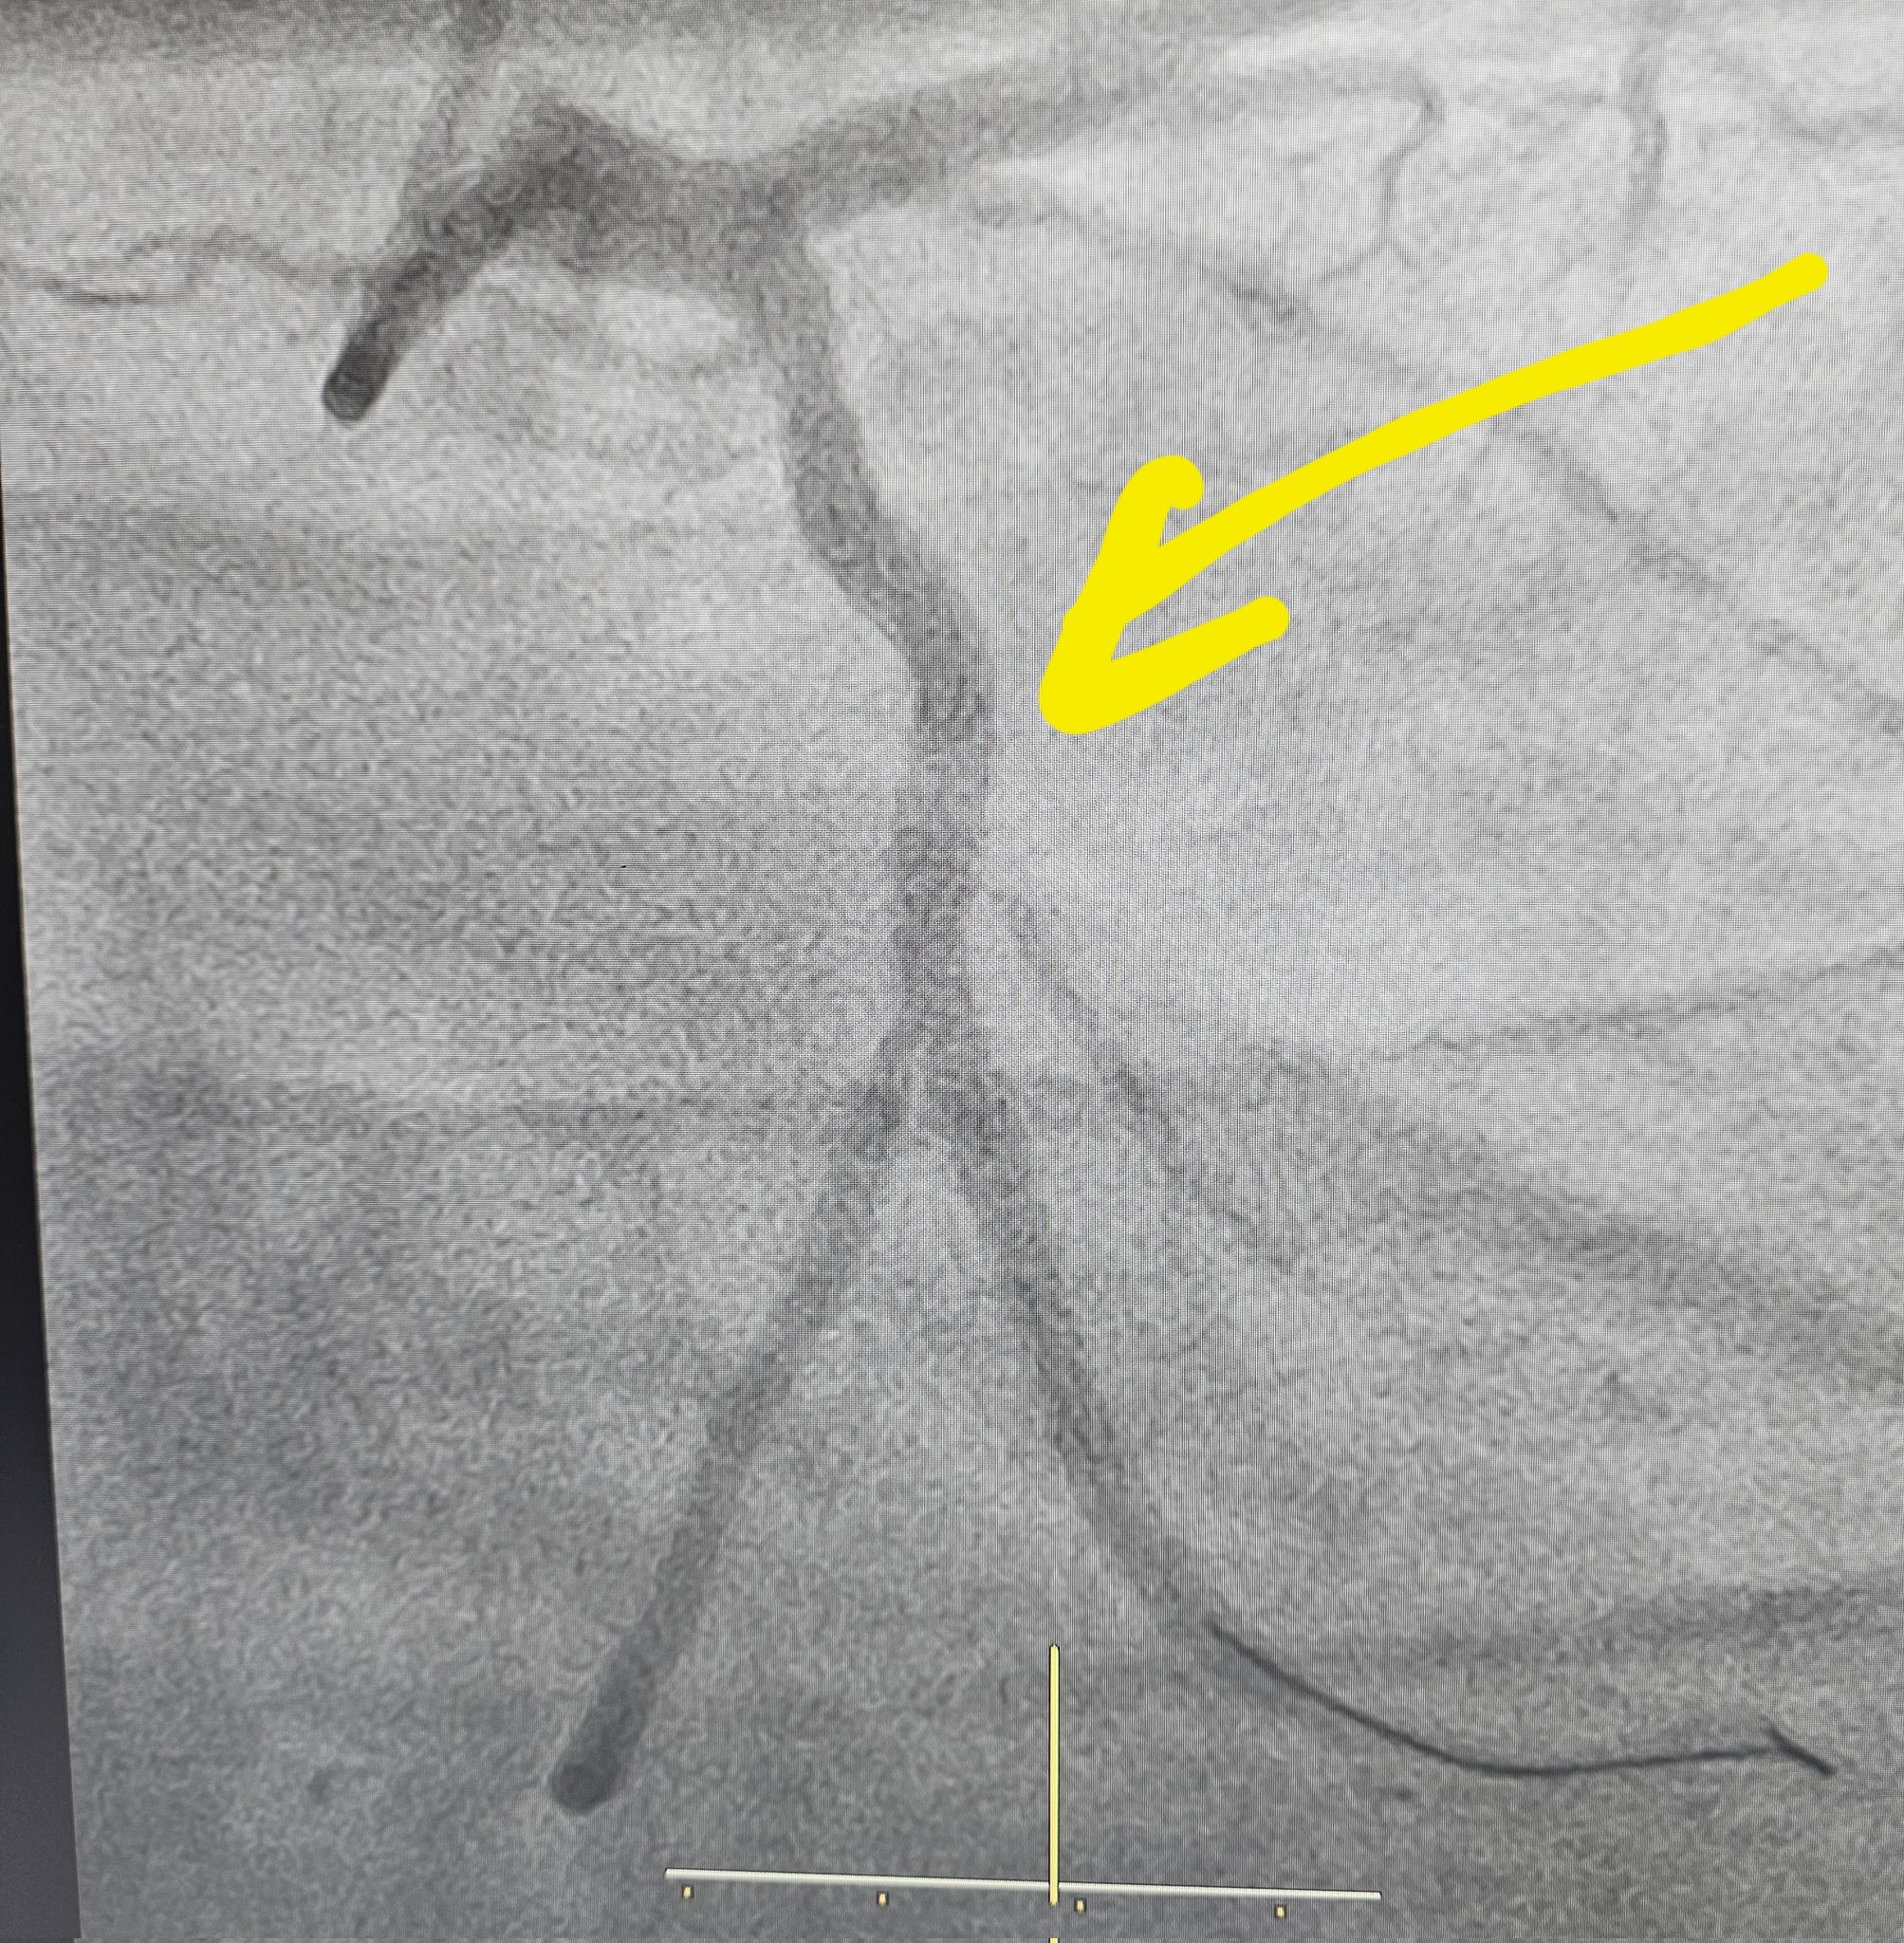

4)Tamim Iqbal:- A surprising addition to the list and quite young for heart related ailment, Tamim Iqbal In March 2025, suffered a heart attack during a match and underwent emergency angioplasty to insert a stent to clear a blockage in one of his arteries. He was discharged from the hospital four days after the procedure and is currently recovering at home, under ongoing medical observation.